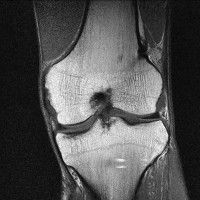

무릎 mri 간단히 봐주실 수 있으시나요 ㅠㅠ

안녕하세요 8년전 십자인대 수술하고 최근 무리한 운동에 무릎 불편감이 생겨서

mri 찍었습니다.

진단결과는 첫 찍은 병원에서 활액막염 이라는 진단을 받았습니다. 혹시 봐주실 수 있으실까요?

올라온 MRI가 단편적이라서 정확한 진단에 어려움이 있지만 십자인대에는 큰 이상이 있지는 않은것 같으며, 무릎관절내 물이 있는 것으로 보아 활액막염의 진단이 맞을 것 같습니다.

하지만 단편적인 영상이기 때문에 촬영병원에서 정확한 판독지 등을 받으시는 것이 좋겠습니다.